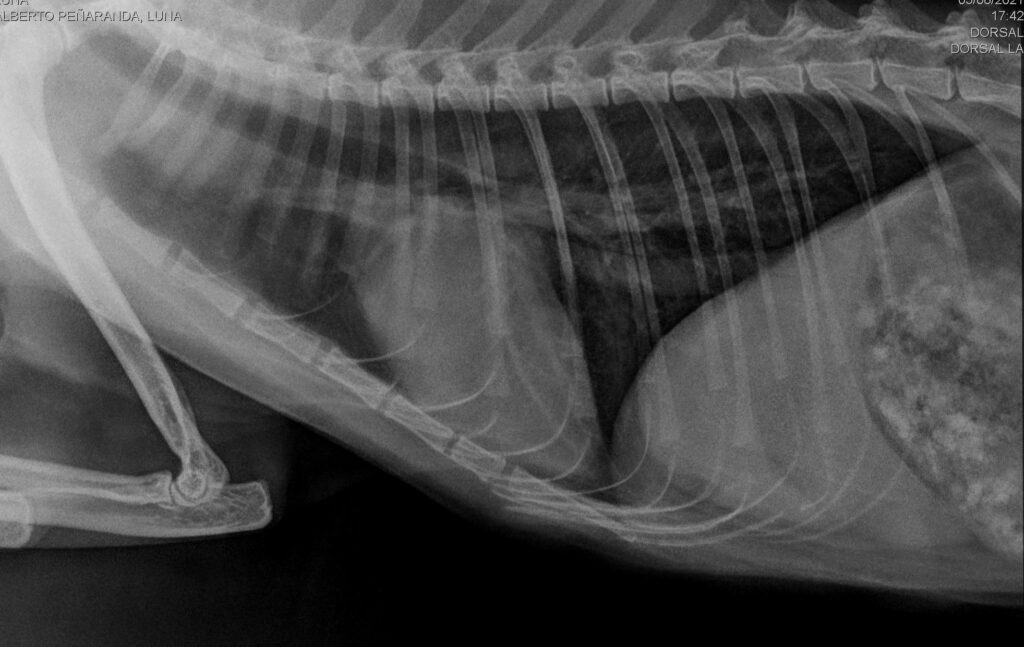

Se llevaron a cabo otras pruebas complementarias consistentes en radiografías de tórax y PCR de Mycoplasmas hemotrópicos sin hallazgos.